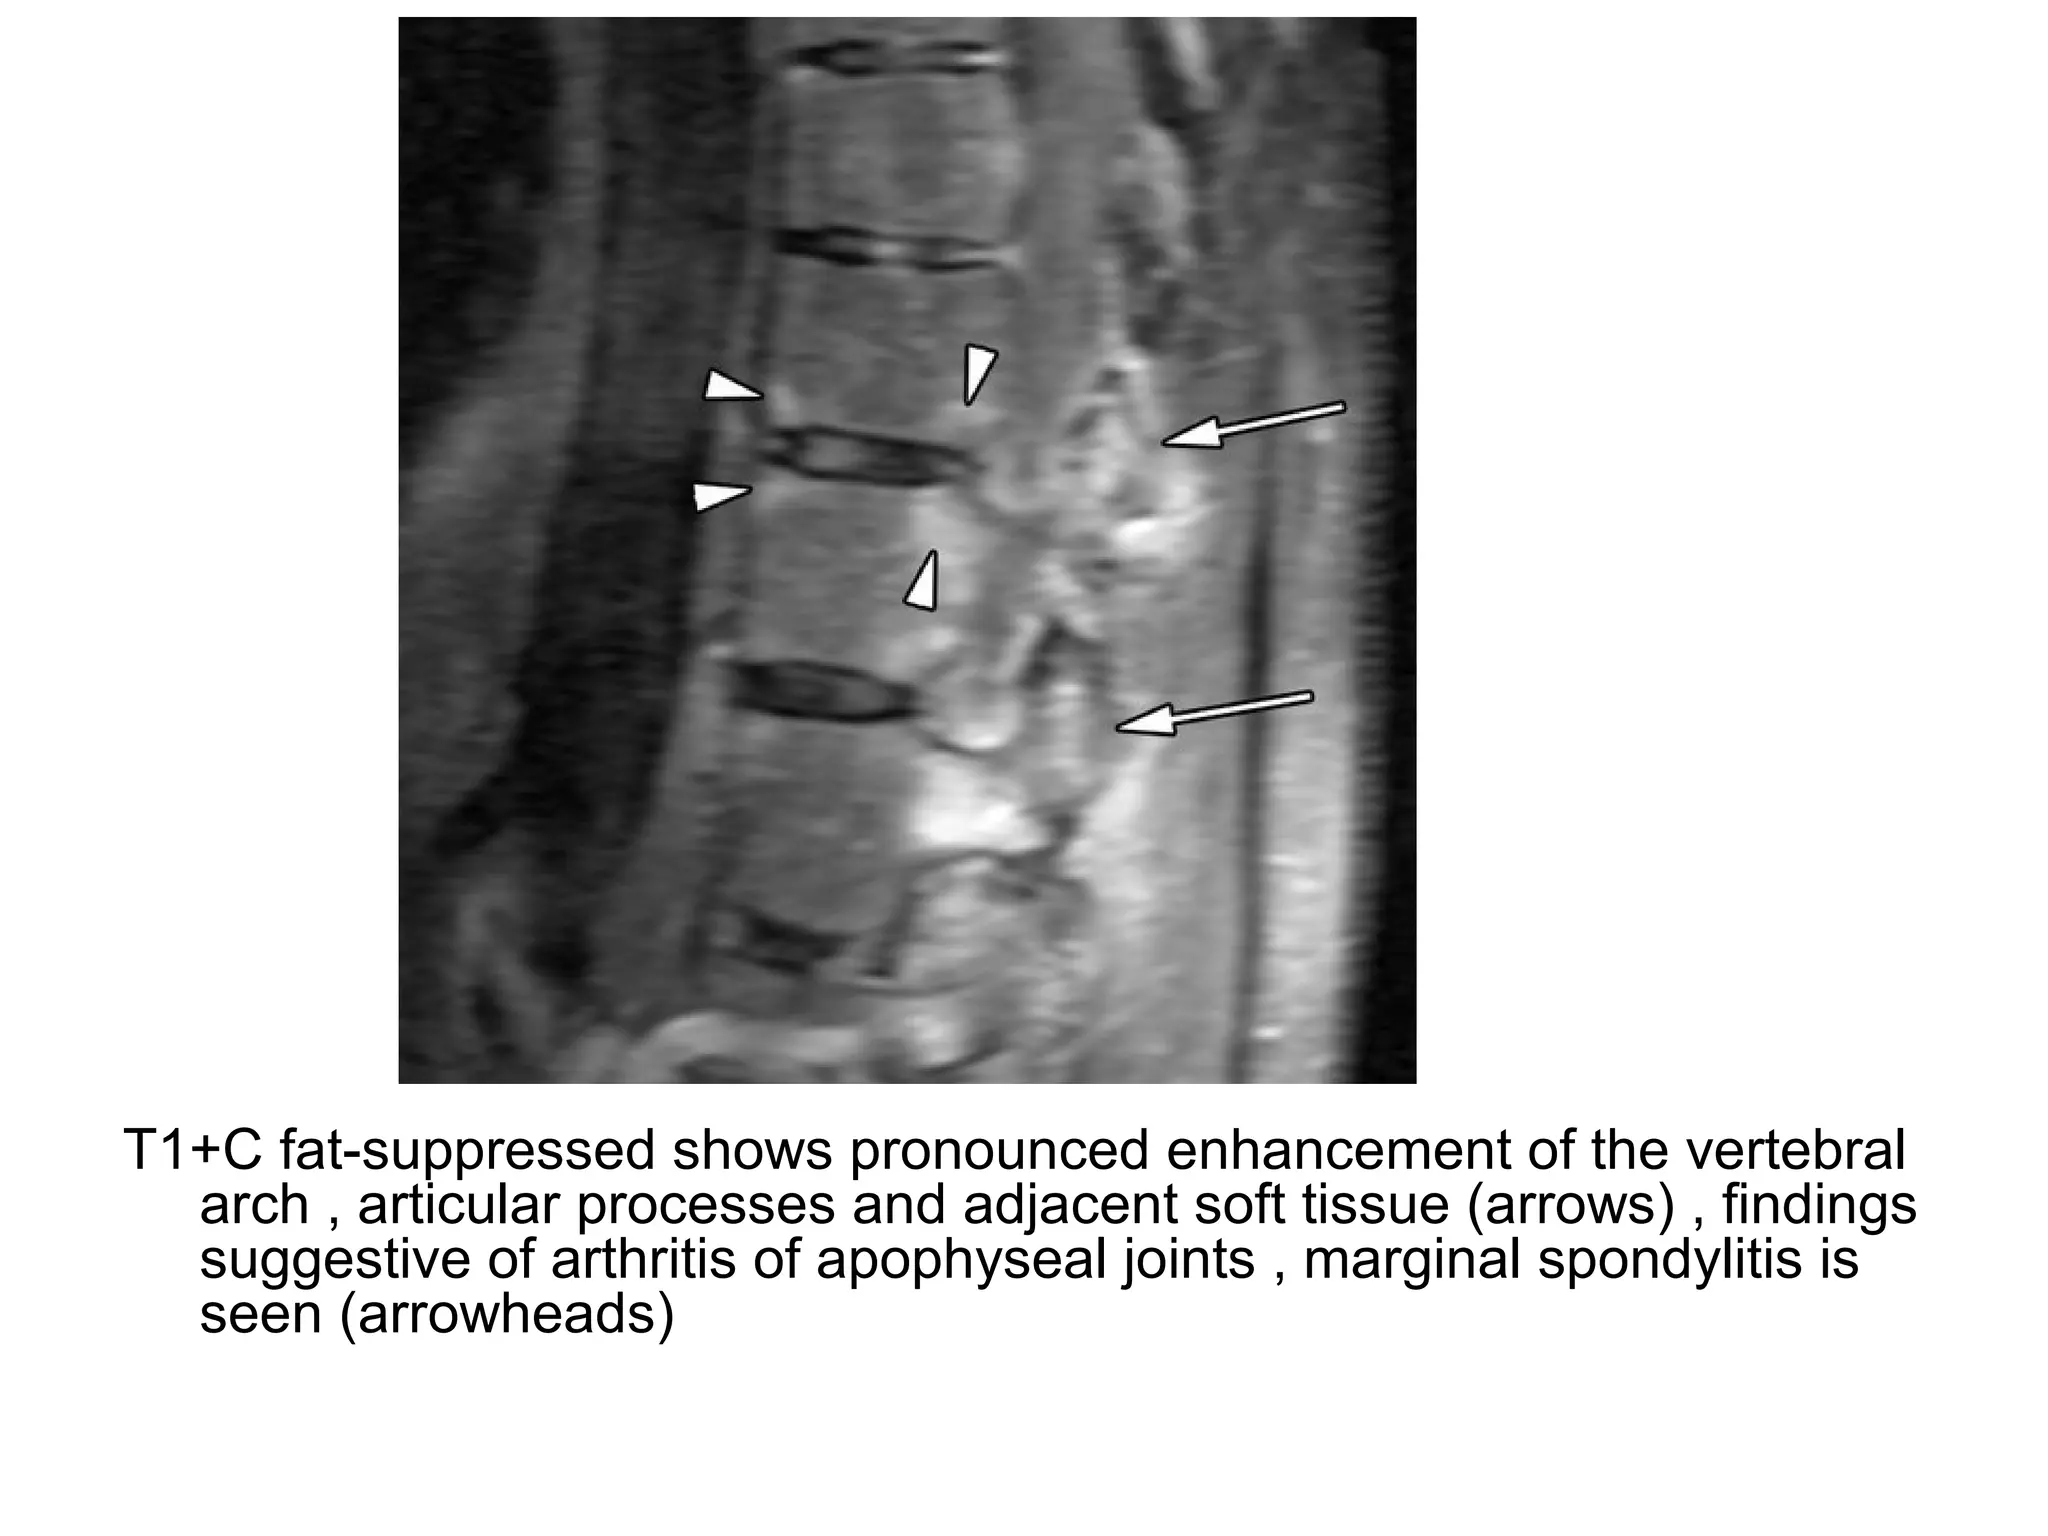

3-Arthritis of the Zygapophyseal Joints :

-May occur with bone marrow edema ,

effusion and erosions and may undergo

ankylosis at the end stage

Sagittal STIR shows hyperintensity of vertebral endplates adjacent to

intervertebral disk , corresponding to Andersson aseptic

spondylodiskitis (arrows) , hyperintensity of bone marrow around

zygapophyseal joints corresponds to arthritis (arrowheads)

T1+C fat-suppressed shows pronounced enhancement of the vertebral

arch , articular processes and adjacent soft tissue (arrows) , findings

suggestive of arthritis of apophyseal joints , marginal spondylitis is

seen (arrowheads)